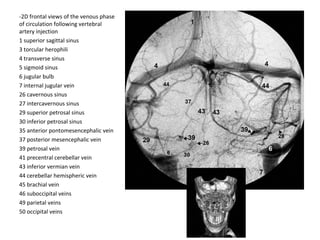

-2D frontal views of the venous phase

of circulation following vertebral

artery injection

1 superior sagittal sinus

3 torcular herophili

4 transverse sinus

5 sigmoid sinus

6 jugular bulb

7 internal jugular vein

26 cavernous sinus

27 intercavernous sinus

29 superior petrosal sinus

30 inferior petrosal sinus

35 anterior pontomesencephalic vein

37 posterior mesencephalic vein

39 petrosal vein

41 precentral cerebellar vein

43 inferior vermian vein

44 cerebellar hemispheric vein

45 brachial vein

46 suboccipital veins

49 parietal veins

50 occipital veins